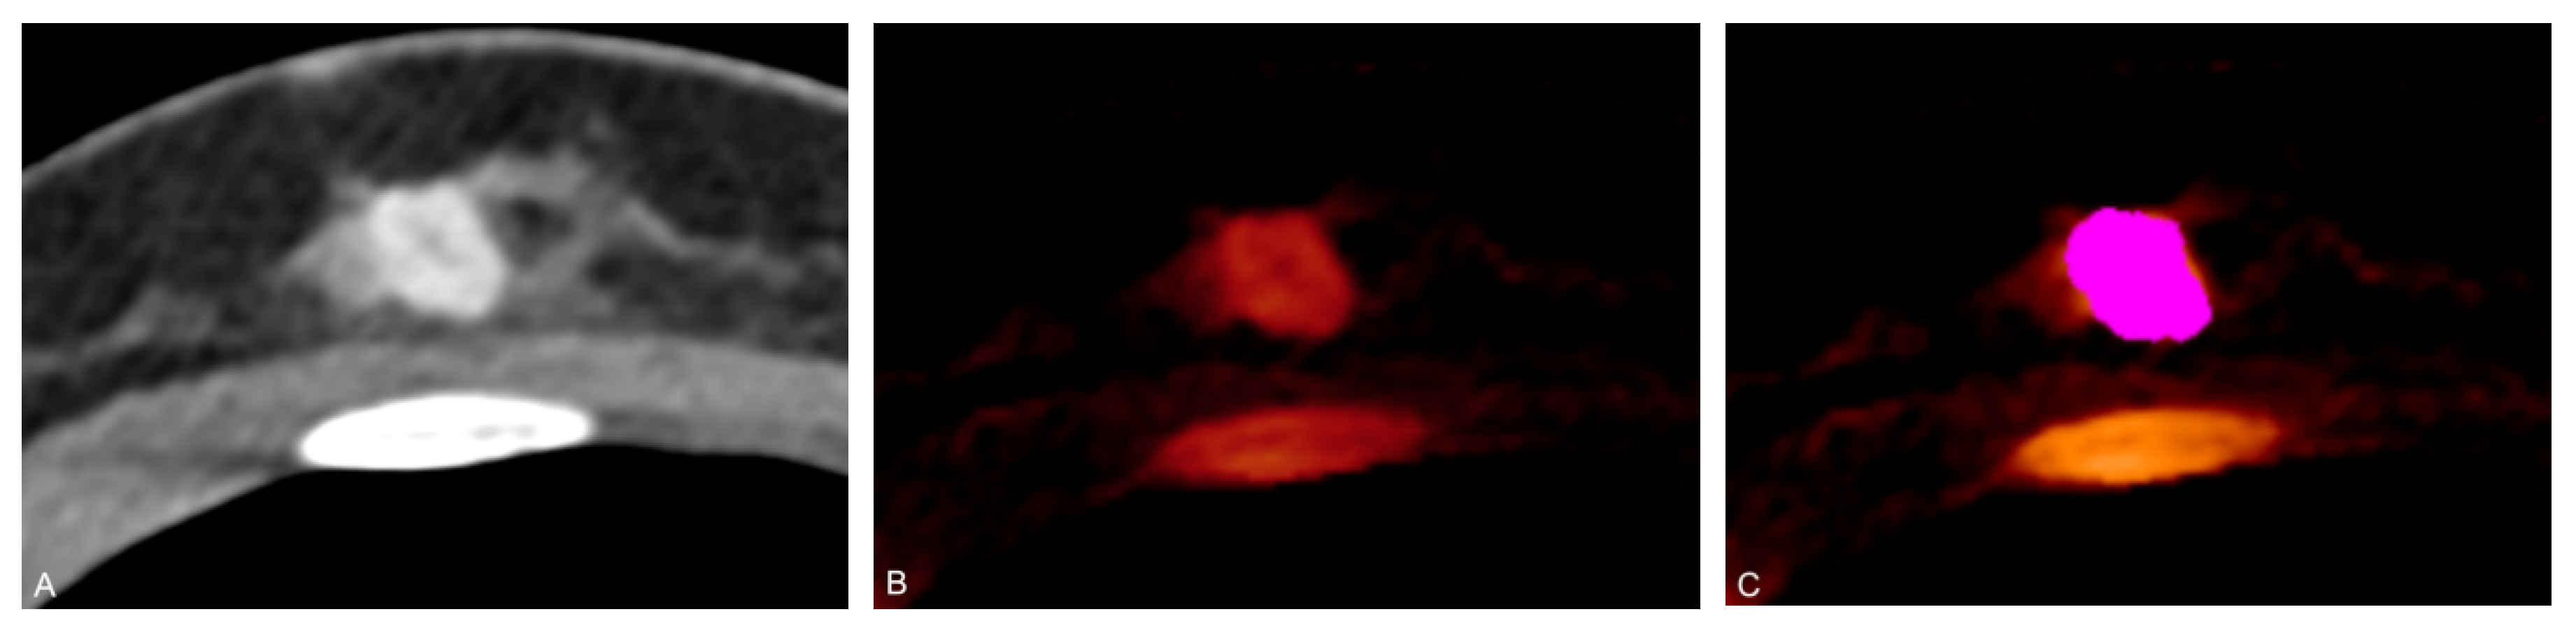

- Zhang, X.; Zheng, C.; Yang, Z.; Cheng, Z.; Deng, H.; Chen, M.; Duan, X.; Mao, J.; Shen, J. Axillary Sentinel Lymph Nodes in Breast Cancer: Quantitative Evaluation at Dual-Energy CT. Radiology 2018, 289, 337–346. [Google Scholar] [CrossRef]

- Zhou, Y.; Su, G.Y.; Hu, H.; Ge, Y.Q.; Si, Y.; Shen, M.P.; Xu, X.Q.; Wu, F.Y. Radiomics analysis of dual-energy CT-derived iodine maps for diagnosing metastatic cervical lymph nodes in patients with papillary thyroid cancer. Eur. Radiol. 2020, 30, 6251–6262. [Google Scholar] [CrossRef] [PubMed]

- Choe, J.; Lee, S.M.; Do, K.H.; Lee, J.B.; Lee, S.M.; Lee, J.G.; Seo, J.B. Prognostic value of radiomic analysis of iodine overlay maps from dual-energy computed tomography in patients with resectable lung cancer. Eur. Radiol. 2019, 29, 915–923. [Google Scholar] [CrossRef] [PubMed]